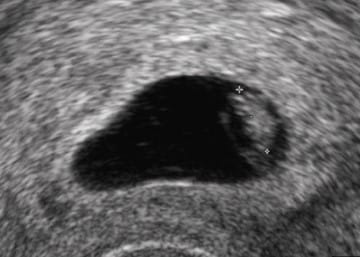

Quand se produit la fécondation après l’ovulation ?

Quand a lieu la fécondation ? On vous dit quand a lieu la fécondation après l’ovulation ainsi que de divers traitements naturels pour tomber enceinte mais aussi garder la grossesse à terme et accoucher...